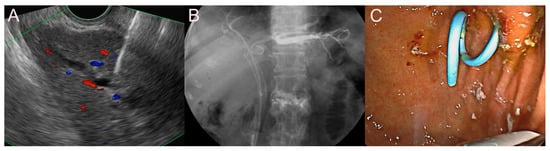

2.2. Stent for EUS-Guided Bile Duct (BD) Drainage

2.2.1. Use of the Plastic Stent

2.2.2. Use of the SEMS

2.2.3. Use of the LAMS